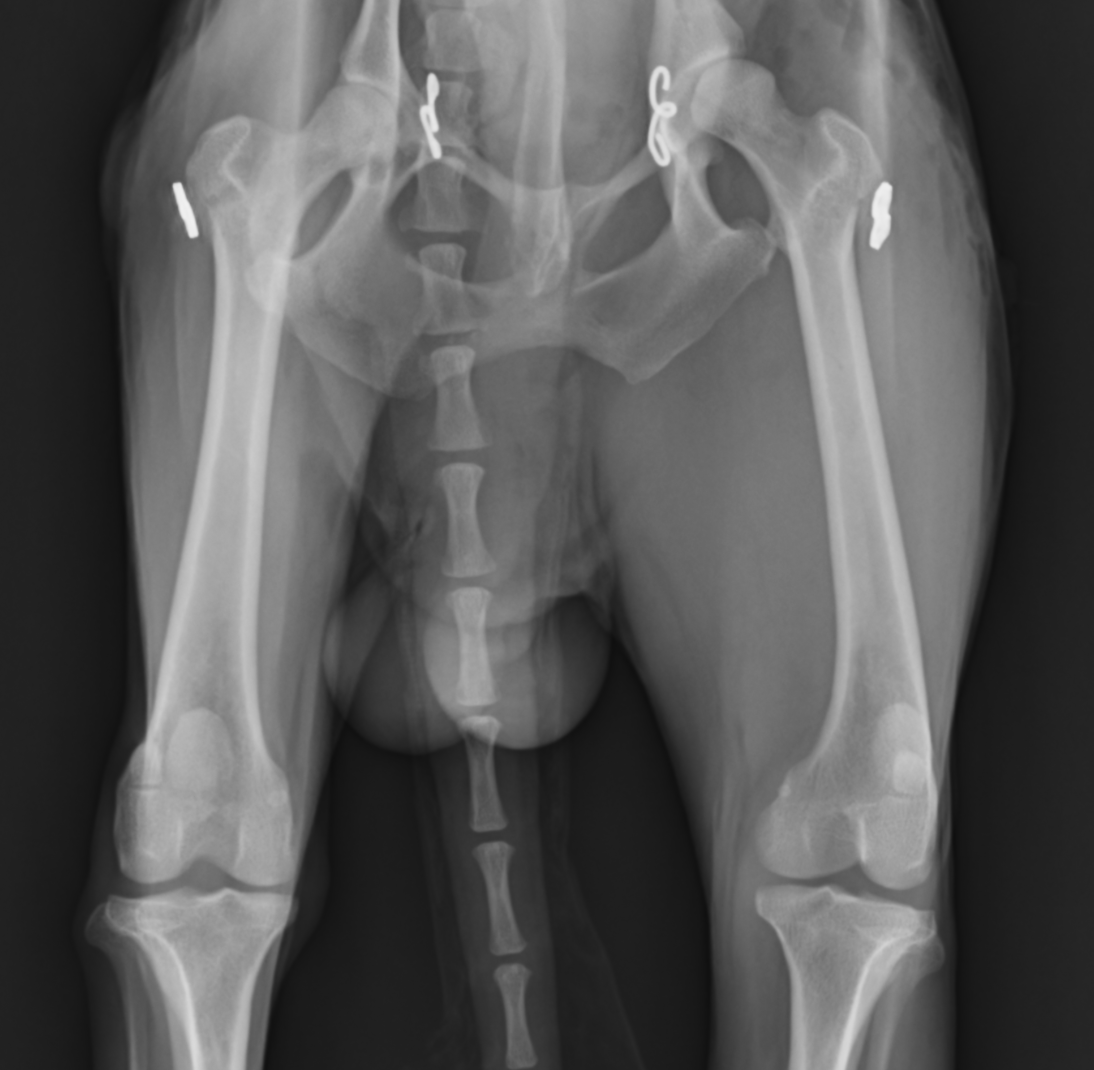

この子は遊んでいたら右後肢を挙上するとのことで来院され、レントゲン画像検査にて右股関節脱臼が確認されました。直ぐに手術を行い脱臼を整復しました。手術にはトグルピン法を行いました。

術後順調に回復していましたが、1ヶ月後には反対足を挙上するとのことで来院され、反対側の脱臼が確認されました。

そのため、すぐに反対足も同様の手術を行うことで脱臼を整復しました。

その後の経過は順調で、すぐに歩行開始し(術後2日目には普通に歩行可能でした)、その後再脱臼もせず、普段どおり生活しているとのことでした。